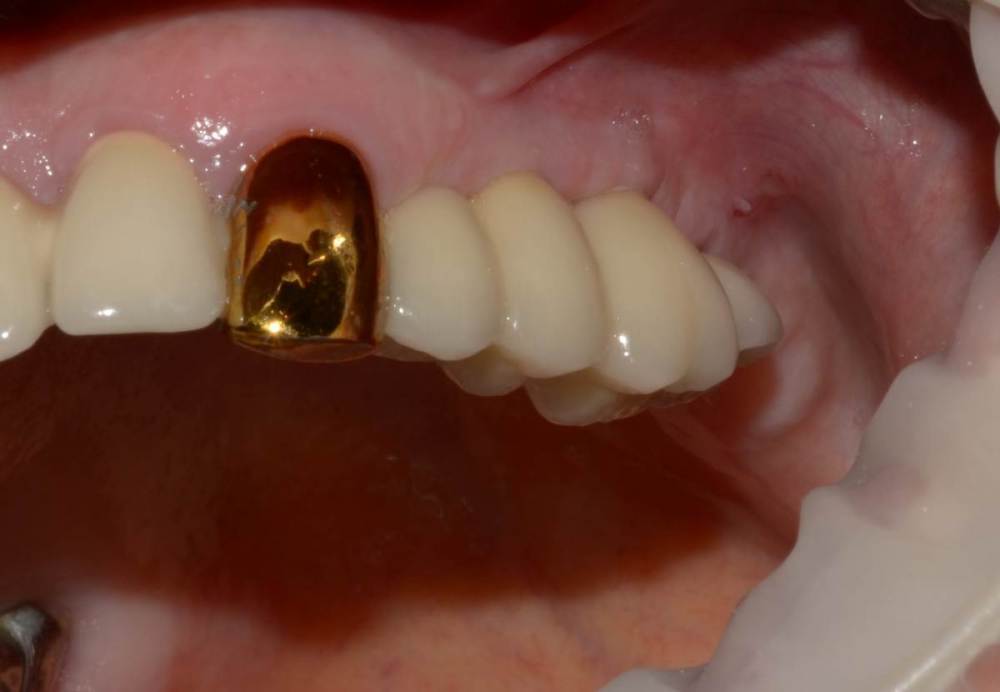

Большой Зеленый Опубликовано 7 ноября, 2022 Поделиться Опубликовано 7 ноября, 2022 @Mailze Если честно ,система не совсем отечественная ,а если совсем честно то она итальянская .ВВ Дентал. Пилят винты в городе Балонья .В 2019 году я был на производстве. Потрясает конечно. Хотели перенести производство в роскосмос или в сколково ,но дальше слов не пошло. Может быть и к лучшему 1 Ссылка на комментарий

Большой Зеленый Опубликовано 7 ноября, 2022 Поделиться Опубликовано 7 ноября, 2022 У Меня много реферативных пациентов . приходят протезироваться на других системах . Фрезерный центр легко изготавливает любые абатменты . Слепочный модуль и аналог купить в эпоху интернета очень просто . Какая нужна распространенность? Ссылка на комментарий

Большой Зеленый Опубликовано 7 ноября, 2022 Поделиться Опубликовано 7 ноября, 2022 У дилера есть премил абатменты. За 10 лет работы проблем никаких не было. 1 Ссылка на комментарий